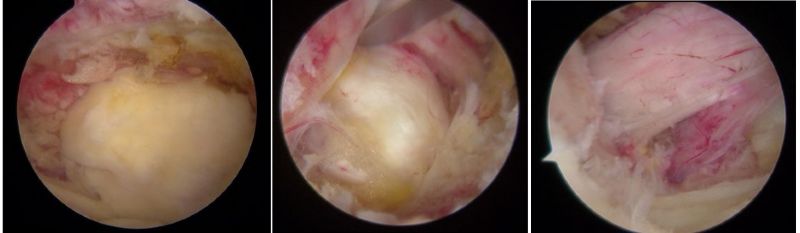

骨科內(nèi)鏡下的腰椎組織

近年來,隨著脊柱內(nèi)鏡技術(shù)突破性發(fā)展,以"精準(zhǔn)減壓、最小侵襲"為核心理念的微創(chuàng)術(shù)式已成為60%以上腰椎手術(shù)患者的優(yōu)先選擇,特別是合并多種疾病、無法耐受開放手術(shù)的高齡患者。相較于傳統(tǒng)開放式手術(shù)需大面積剝離肌肉組織、損傷脊柱穩(wěn)定性的弊端,該技術(shù)通過直徑僅7-8毫米的骨科內(nèi)鏡工作通道,在局部麻醉下借助高清內(nèi)鏡可視化系統(tǒng)精準(zhǔn)定位病灶,實現(xiàn)了"靶點精準(zhǔn)治療"的突破性進(jìn)展。

UBE是unlateral、biportal、endoscopic三個英文單詞的首字母,也就是“單側(cè)雙通道脊柱內(nèi)鏡”。臨床上簡稱為:“UBE”。其技術(shù)的核心是雙通道:一個是內(nèi)鏡通道,另一個是器械操作通道,兩處皮膚切口各僅約0.8cm。與傳統(tǒng)開放手術(shù)相比,它借助天然解剖間隙建立微創(chuàng)工作通道,解除神經(jīng)壓迫。對椎旁肌肉損傷較小,且能夠最大程度地保留完整的脊柱結(jié)構(gòu),維持了術(shù)后脊柱的穩(wěn)定,具有創(chuàng)傷小、出血少、恢復(fù)良好、并發(fā)癥少、費用低等優(yōu)點,大幅提升了手術(shù)的效率和安全性。